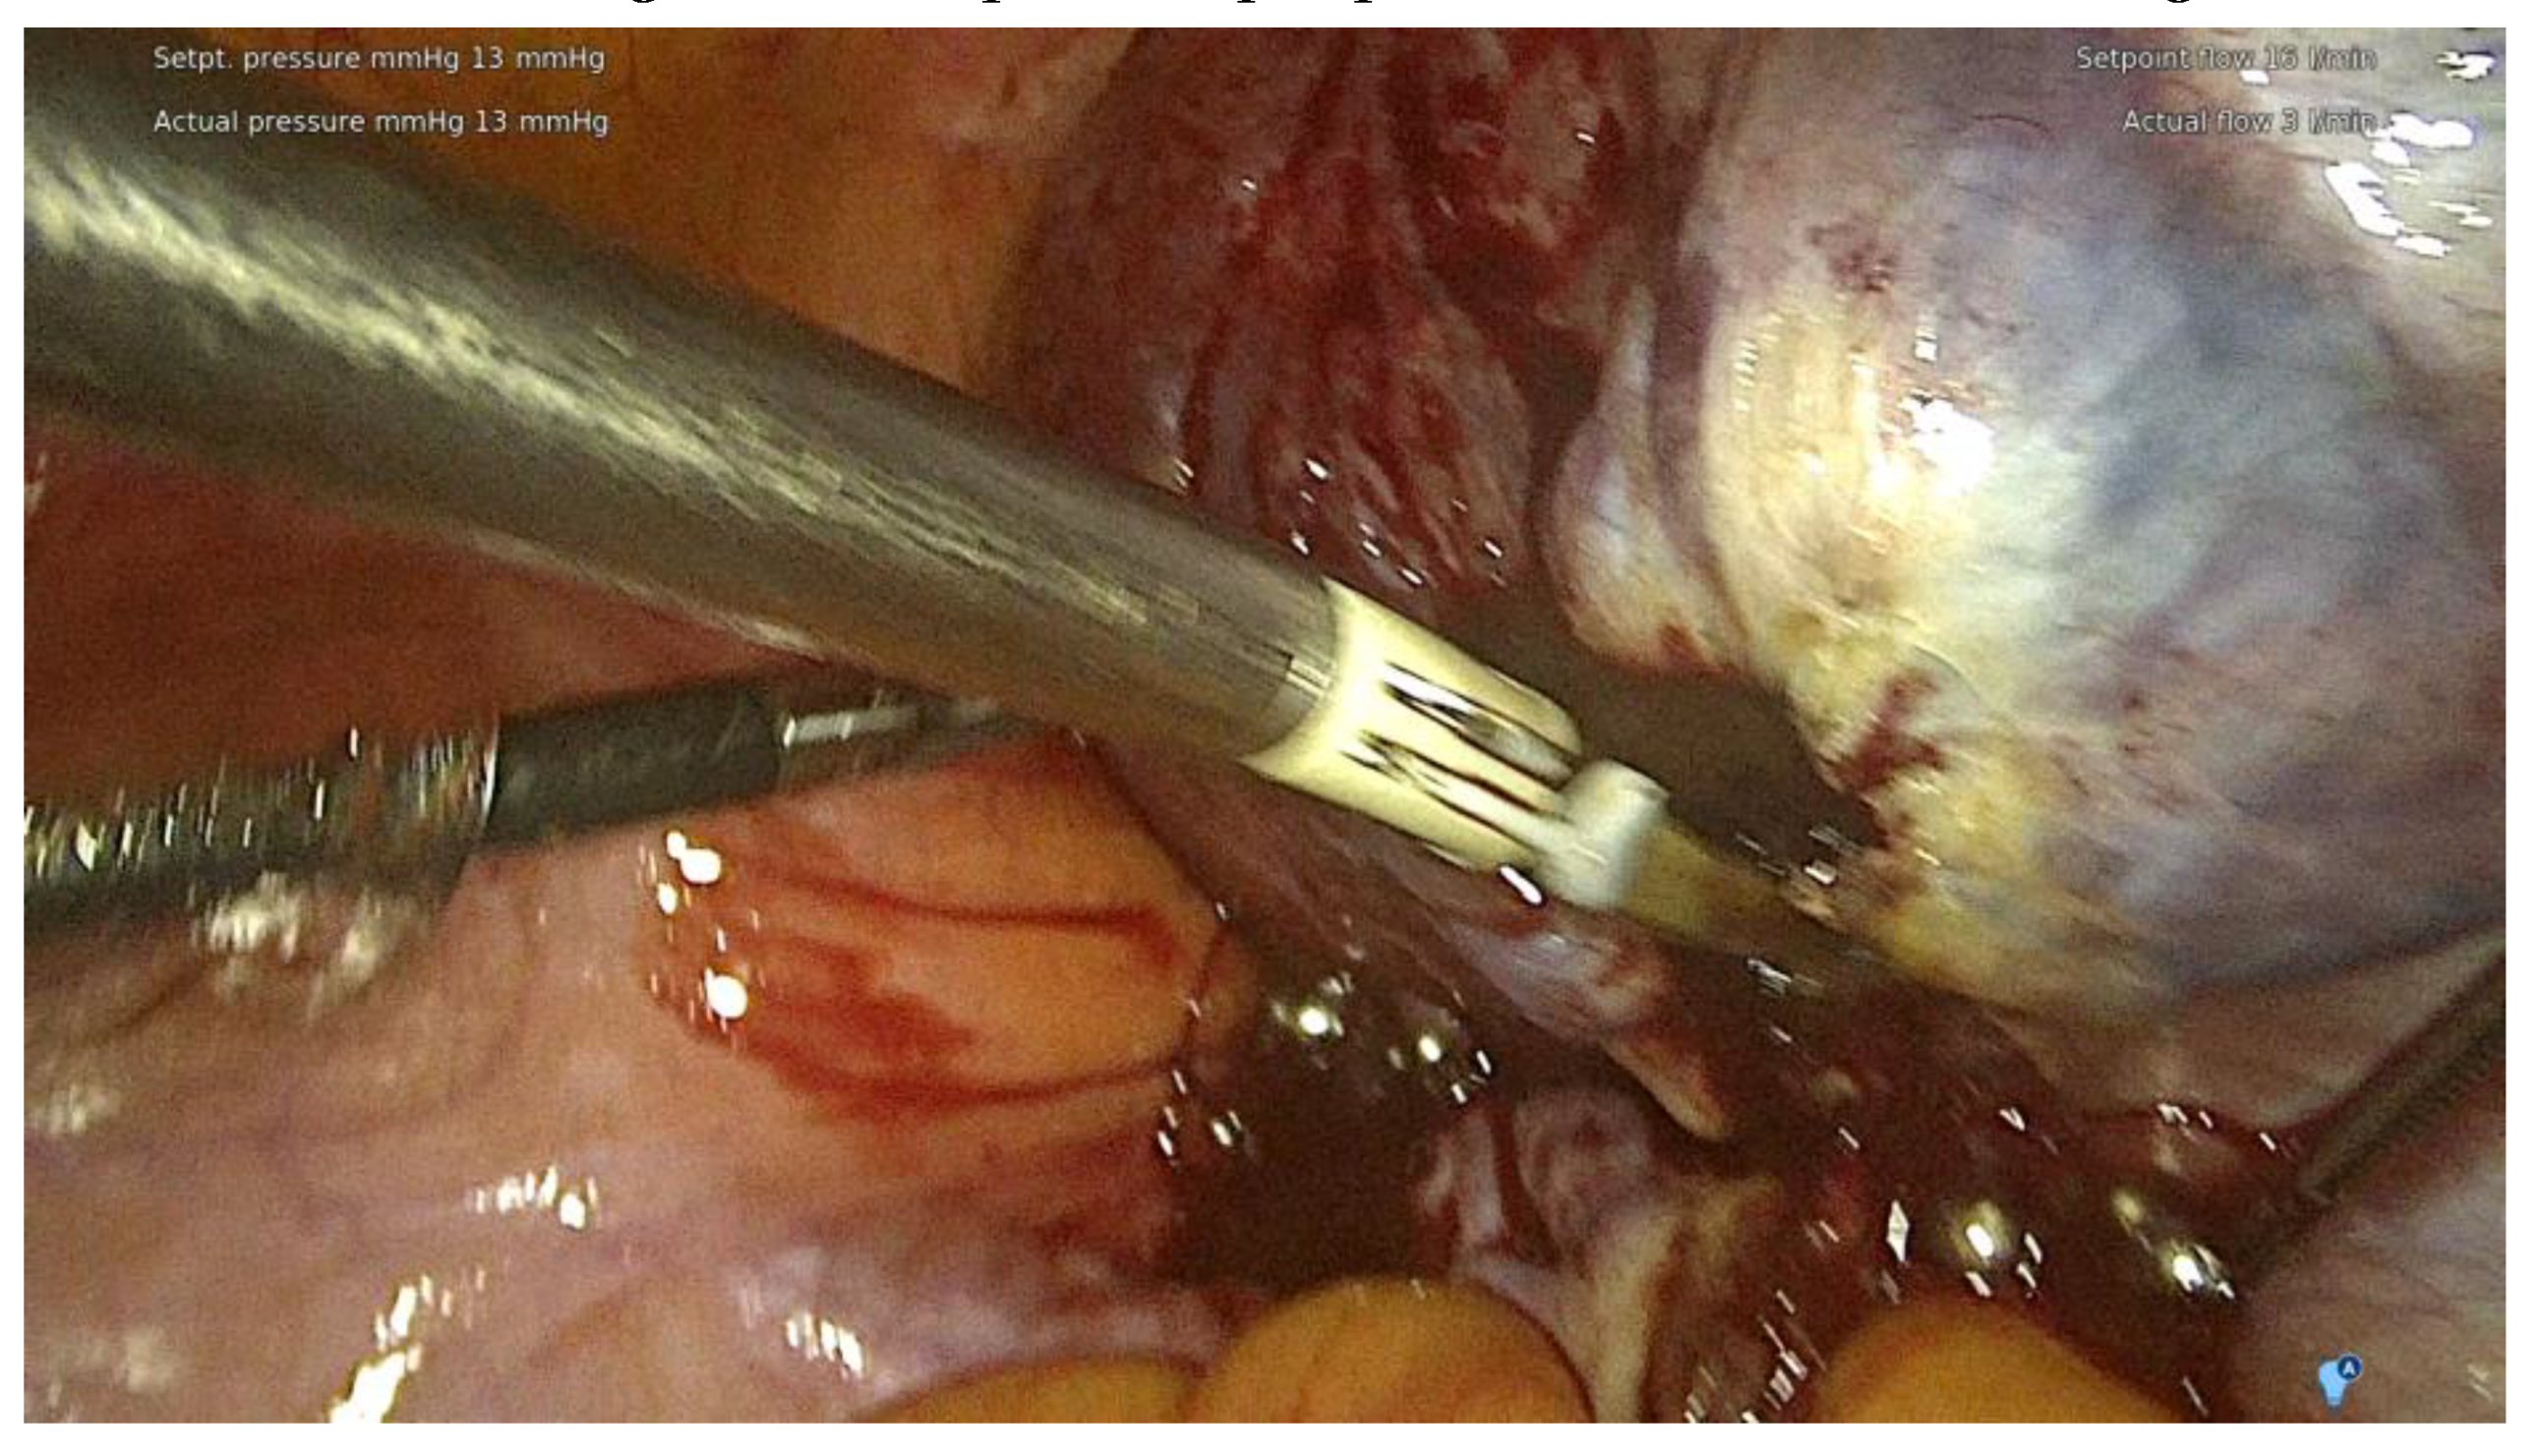

The range of the surgery was wide and consisted of modified radical hysterectomy, unilateral or bilateral infiltration of USLs and RVS resection, unilateral or bilateral ovarian cystectomy or drainage, large bowel resection procedures ( shaving, discoid resection, segmental resection of the rectum, sigmoid colon, caecum) , partial bladder resection, unilateral or bilateral ureterolysis sometimes with ureteral retransplantation, small intestine segmental resection, adnexectomy, nephrectomy, diaphragmatic lesions resection, bone, nerve and vessel lesion resection, and 2 cases of thoracic interventions. An image of the laparoscopic procedure is shown in Figure 3.

Figure 3. Intraoperative image of laparoscopic procedure – deep endometriosis.